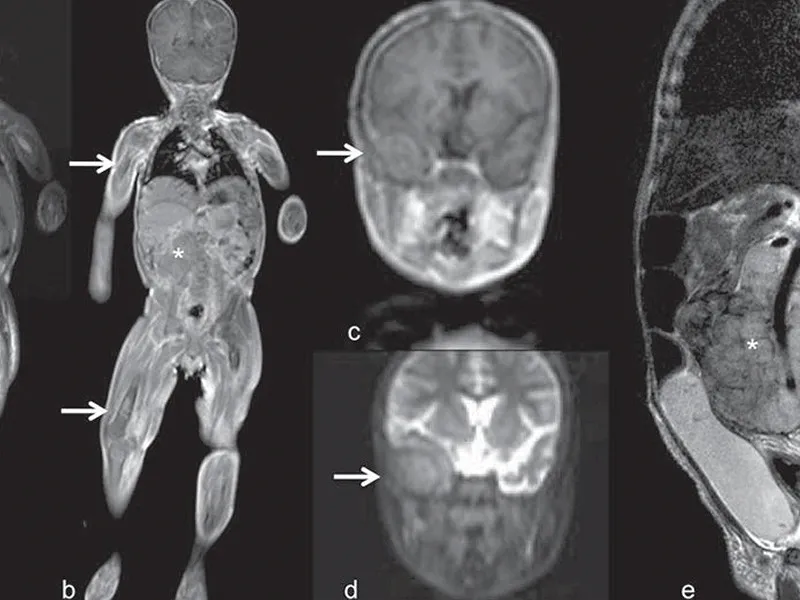

Tüm vücut MR, genellikle hastalıkların erken teşhisi ve yayılımının değerlendirilmesi amacıyla çekilir. Özellikle kanser taramaları, inflamatuar hastalıklar, enfeksiyonlar ve dejeneratif hastalıkların tespitinde kullanılır. Ayrıca, vücutta mevcut olan anormalliklerin detaylı bir şekilde incelenmesi için de tercih edilir.

Tüm vücut MR, kanser şüphesi olan hastalarda, inflamatuar hastalıklarda, enfeksiyonların yayılımını belirlemek için ve dejeneratif hastalıkların teşhisinde kullanılır. Ayrıca, kronik ağrıların kaynağını tespit etmek, sinir sistemi hastalıklarını ve damar problemlerini değerlendirmek amacıyla da uygulanabilir.

Tüm vücut MR ile kanser türleri, tümörlerin yayılımı, inflamatuar hastalıklar, enfeksiyonlar, dejeneratif hastalıklar, sinir sistemi bozuklukları ve damar hastalıkları teşhis edilebilir. Bu yöntem, özellikle erken teşhis gerektiren hastalıklarda büyük önem taşır ve doktorların doğru tedavi yöntemini belirlemelerine yardımcı olur.